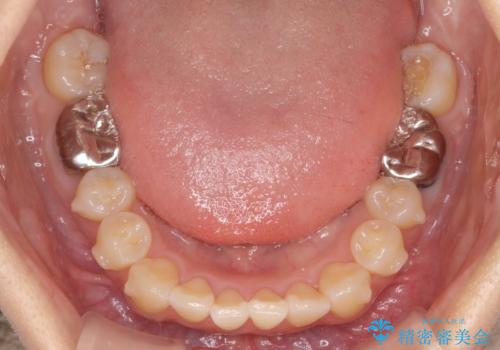

- 噛んだ時の前歯正中のズレ、引っ込んでいる前歯を治したい。と矯正治療を希望され来院されました。

左上2の前歯はスペースが足りないため、後方に引っ込んでしまっている状態です。

マウスピース矯正システムインビザラインで歯の後方移動、咬合関係の修正を行ったのち、引っ込んでいる左上2をワイヤーを用いて短時間で引き出す治療計画としました。

部分ワイヤー矯正を行なったことで約3ヶ月という短期間で前歯を綺麗に並べることができました。